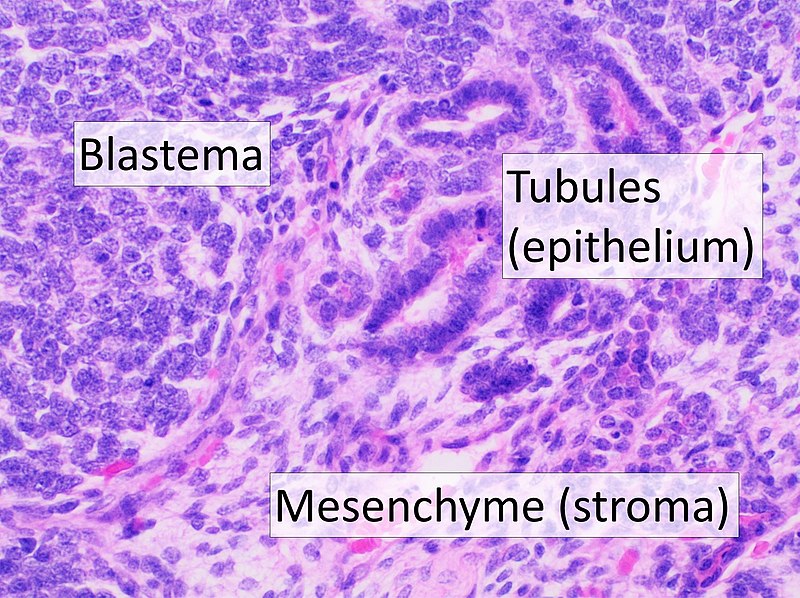

Wilms Tumor

Wilms tumor is a malignant kidney tumor composed of primitive glomeruli, tubules, and stromal cells blastema which is an immature kidney mesenchyme.

Wilms tumor is associated with WT1 mutation, especially in syndromic cases.